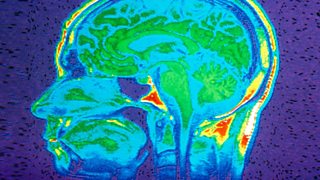

Our brains are made of 100 billion neurons. If you were to count all the neurons in your brain at a rate of one a second, it would take more than 3,000 years.

Our minds are made of molecular machines, aka brain cells. And if you find this depressing then you lack imagination, says Dennett. “Do you know the power of a machine made of a trillion moving parts?” he asks.